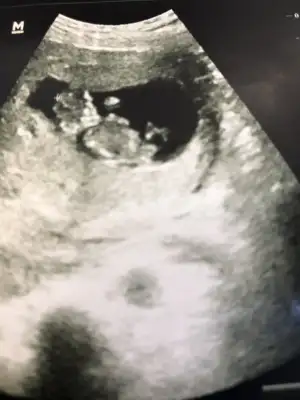

Merhabalar. Beş haftalıkken yuvarlak bir kesenin tam solundaydı ama 7 haftalıkken görüntü böyle ortada çıktı. Cinsiyet tahmini yapılabilir mi bundan da?